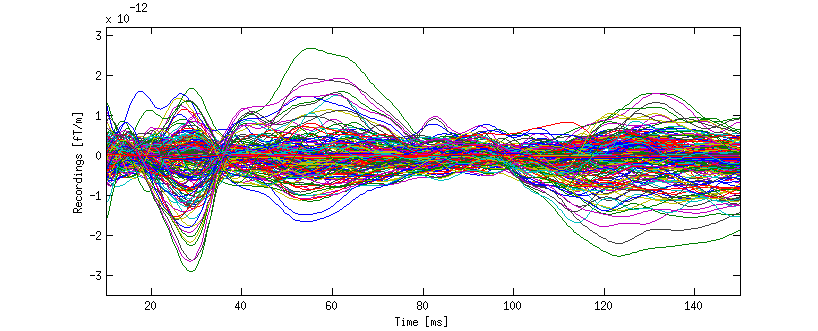

Data from a Somatosensory Evoked Fields (SEFs) mapping experiment were acquired. The recordings were performed at Istituto Neurologico Carlo Besta, Milano (Italy), by means of a –channel MEG device (Elekta Neuromag Oy, Helsinki, Finland) comprising planar gradiometers and magnetometers in a helmet–shaped array. Informed consent and prior approval by the local ethics committee were obtained before the recording session. The position of the subject’s head within the MEG helmet with respect to anatomical MRIs, obtained by using a –Tesla MRI device (General Electric, Milwaukee, USA), was determined by means of a D digitizer and four head position indicator coils. The left median nerve at wrist was electrically stimulated at the motor threshold. The MEG signals were recorded at a sampling frequency of Hz and then band–pass filtered in the window Hz. Eye movements were monitored by Electrooculogram (EOG) in order to exclude artifacts from the MEG recordings: trials with EOG or MEG exceeding mV or pT/cm, respectively, were neglected and 69 clean trials were averaged. The signal space separation method described in (Taulu, Kajola and Simola, 2004) was used to reduce external interference.

The final, averaged data used in our study are plotted in Figure 3. The plot appears to confirm that there are three main temporal windows of interest: one between 20 and 35, one between 45 and 75, the last one starting around 110 milliseconds after stimulus.